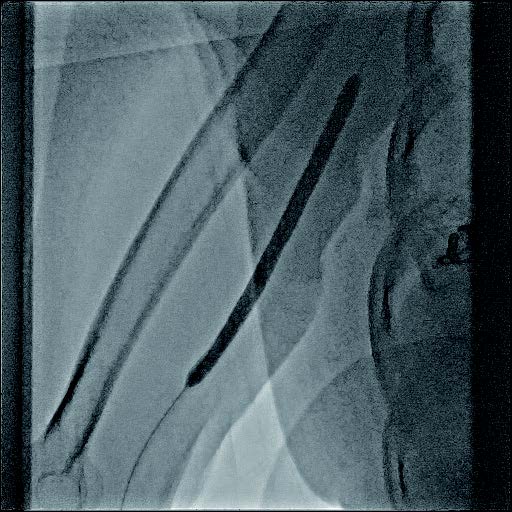

実際の治療

バイアバーン® ステントグラフト留置の手技については、当施設では概ね毎回同じ手技を実施している。ステントグラフトの長さについては病変に依存するが、径については6 mmの人工血管に対して、7 mmのバイアバーン® ステントグラフトを留置している。

静脈とはいえ、透析患者においては硬化性変化が強い病変が多く、indentation を残さずに pre dilatation をかけておくことが重要と考えられる。そこで、径7 mmのバイアバーン® ステントグラフト留置前に、径6 mmの高耐圧バルーンにてしっかり拡張し、indentationを残さないことを確認した。バイアバーン® ステントグラフト留置後もバルーンでステント内、特に人工血管とのオーバーラップ部位にしっかり圧をかけて後拡張を行っている。

また、バイアバーン® ステントグラフトは、位置決めをした後の留置時に移動する事象は自施設で行った症例ではほとんど認めていないが、展開時のstabilityを保つため0.018 inchのサポートワイヤーを用いることが多い。当患者においても、上記手技を行い良好なinitial successを得られた。他症例もほぼ同一の手技で行っているがサイズなどで問題になった症例は、本稿の執筆時点では経験していない。